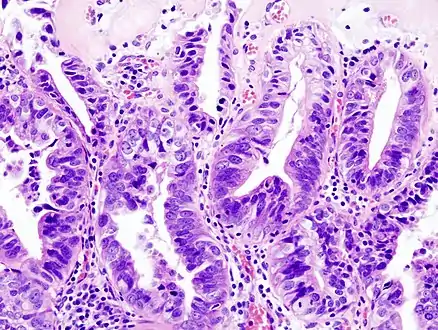

Gallbladder adenocarcinoma histopathology